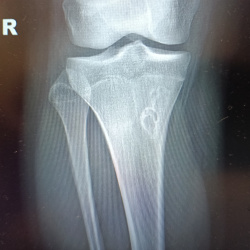

Коллеги, здравствуйте! Мужчина, 40 лет, жалобы на боли в правом коленном суставе.  По снимкам - много вопросов. 1) Что с бугристостью большеберцовой кости? Экзостоз? Вроде как...